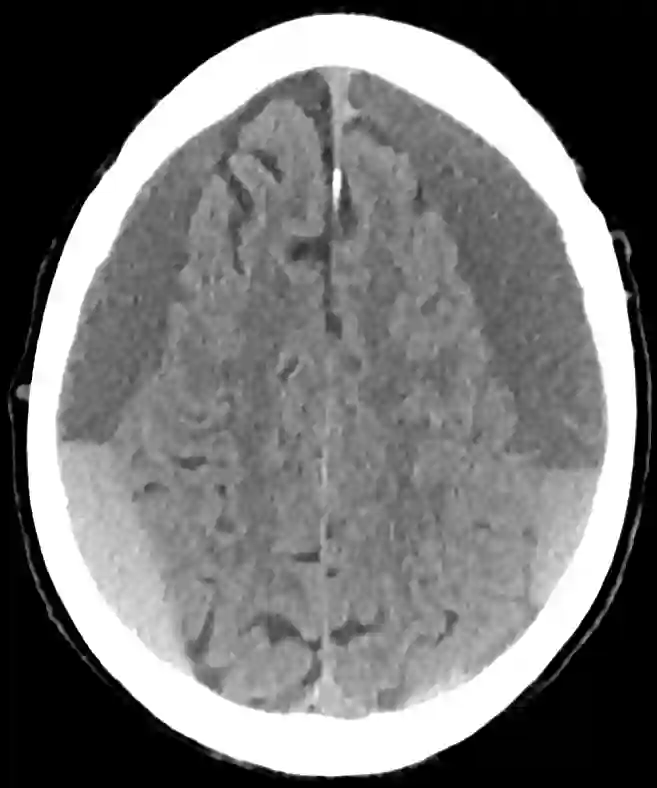

Chronisches Subduralhämatom im CT.

Patient mit einem chronischen Subduralhämatom auf der linken Seite in einem axialen CT-Bild.